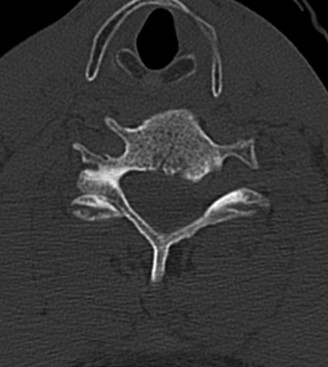

Initial trauma radiographs demonstrated a loss of anterior and middle column height at L1, with a focal kyphotic deformity. However, plain films are vastly insufficient for definitive surgical planning in thoracolumbar trauma. A high-resolution, fine-cut Computed Tomography (CT) scan of the entire spine was obtained. The CT images confirmed an L1 burst fracture with severe comminution of the vertebral body. Sagittal and axial reconstructions revealed 50% canal compromise secondary to a large retropulsed bone fragment originating from the posterosuperior aspect of the L1 vertebral body. Furthermore, the CT demonstrated 25 degrees of segmental kyphosis measured from the superior endplate of T12 to the inferior endplate of L1.

A critical finding on the axial CT slices was a vertical, split fracture propagating through the L1 lamina. This is a highly significant morphological feature. A lamina fracture in the setting of a burst fracture with retropulsion strongly correlates with a dural tear and potential entrapment of the cauda equina nerve roots. When the vertebral body bursts posteriorly, the pedicles are driven outward, and the lamina fractures as the spinal canal attempts to expand to accommodate the retropulsed bone. If the dura is lacerated, nerve roots can herniate through the dural defect and become incarcerated in the laminar fracture site.